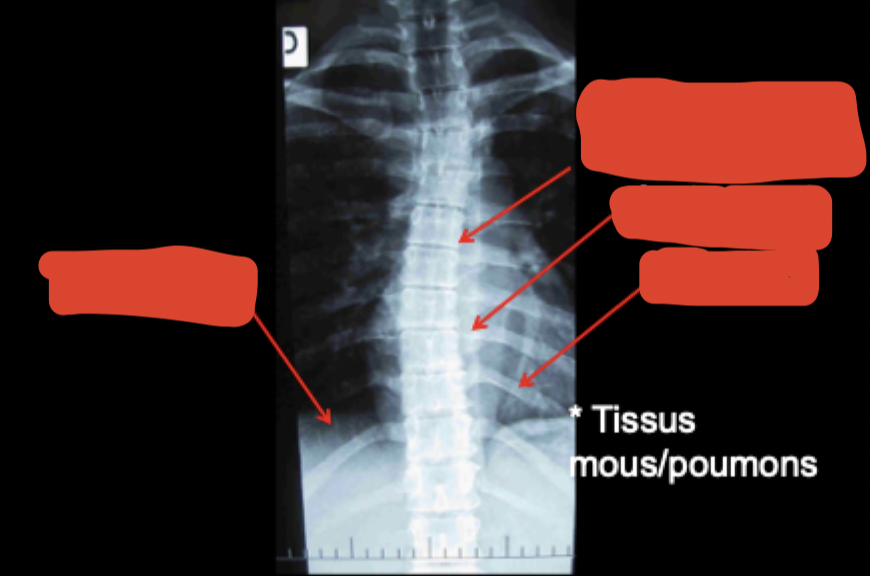

Vue AP permet de voir quoi?

• Alignement (corps, pédicules)

• Symétrie espaces IV

• Scoliose

• Ombrage (ligne para-vertébrale, coeur, aorte, diaphragme)

Identifier